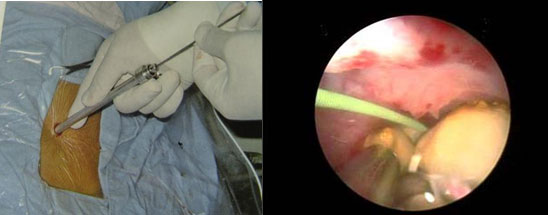

g.前列腺癌粒子植入术

h.女性压力性尿失禁尿道中段悬吊术

手术时间仅为20分钟左右,患者恢复快,创伤小,而且身体表面没有任何切口。是目前国际上治疗女性压力性尿失禁的金标准,具有长期的安全性和有效性。